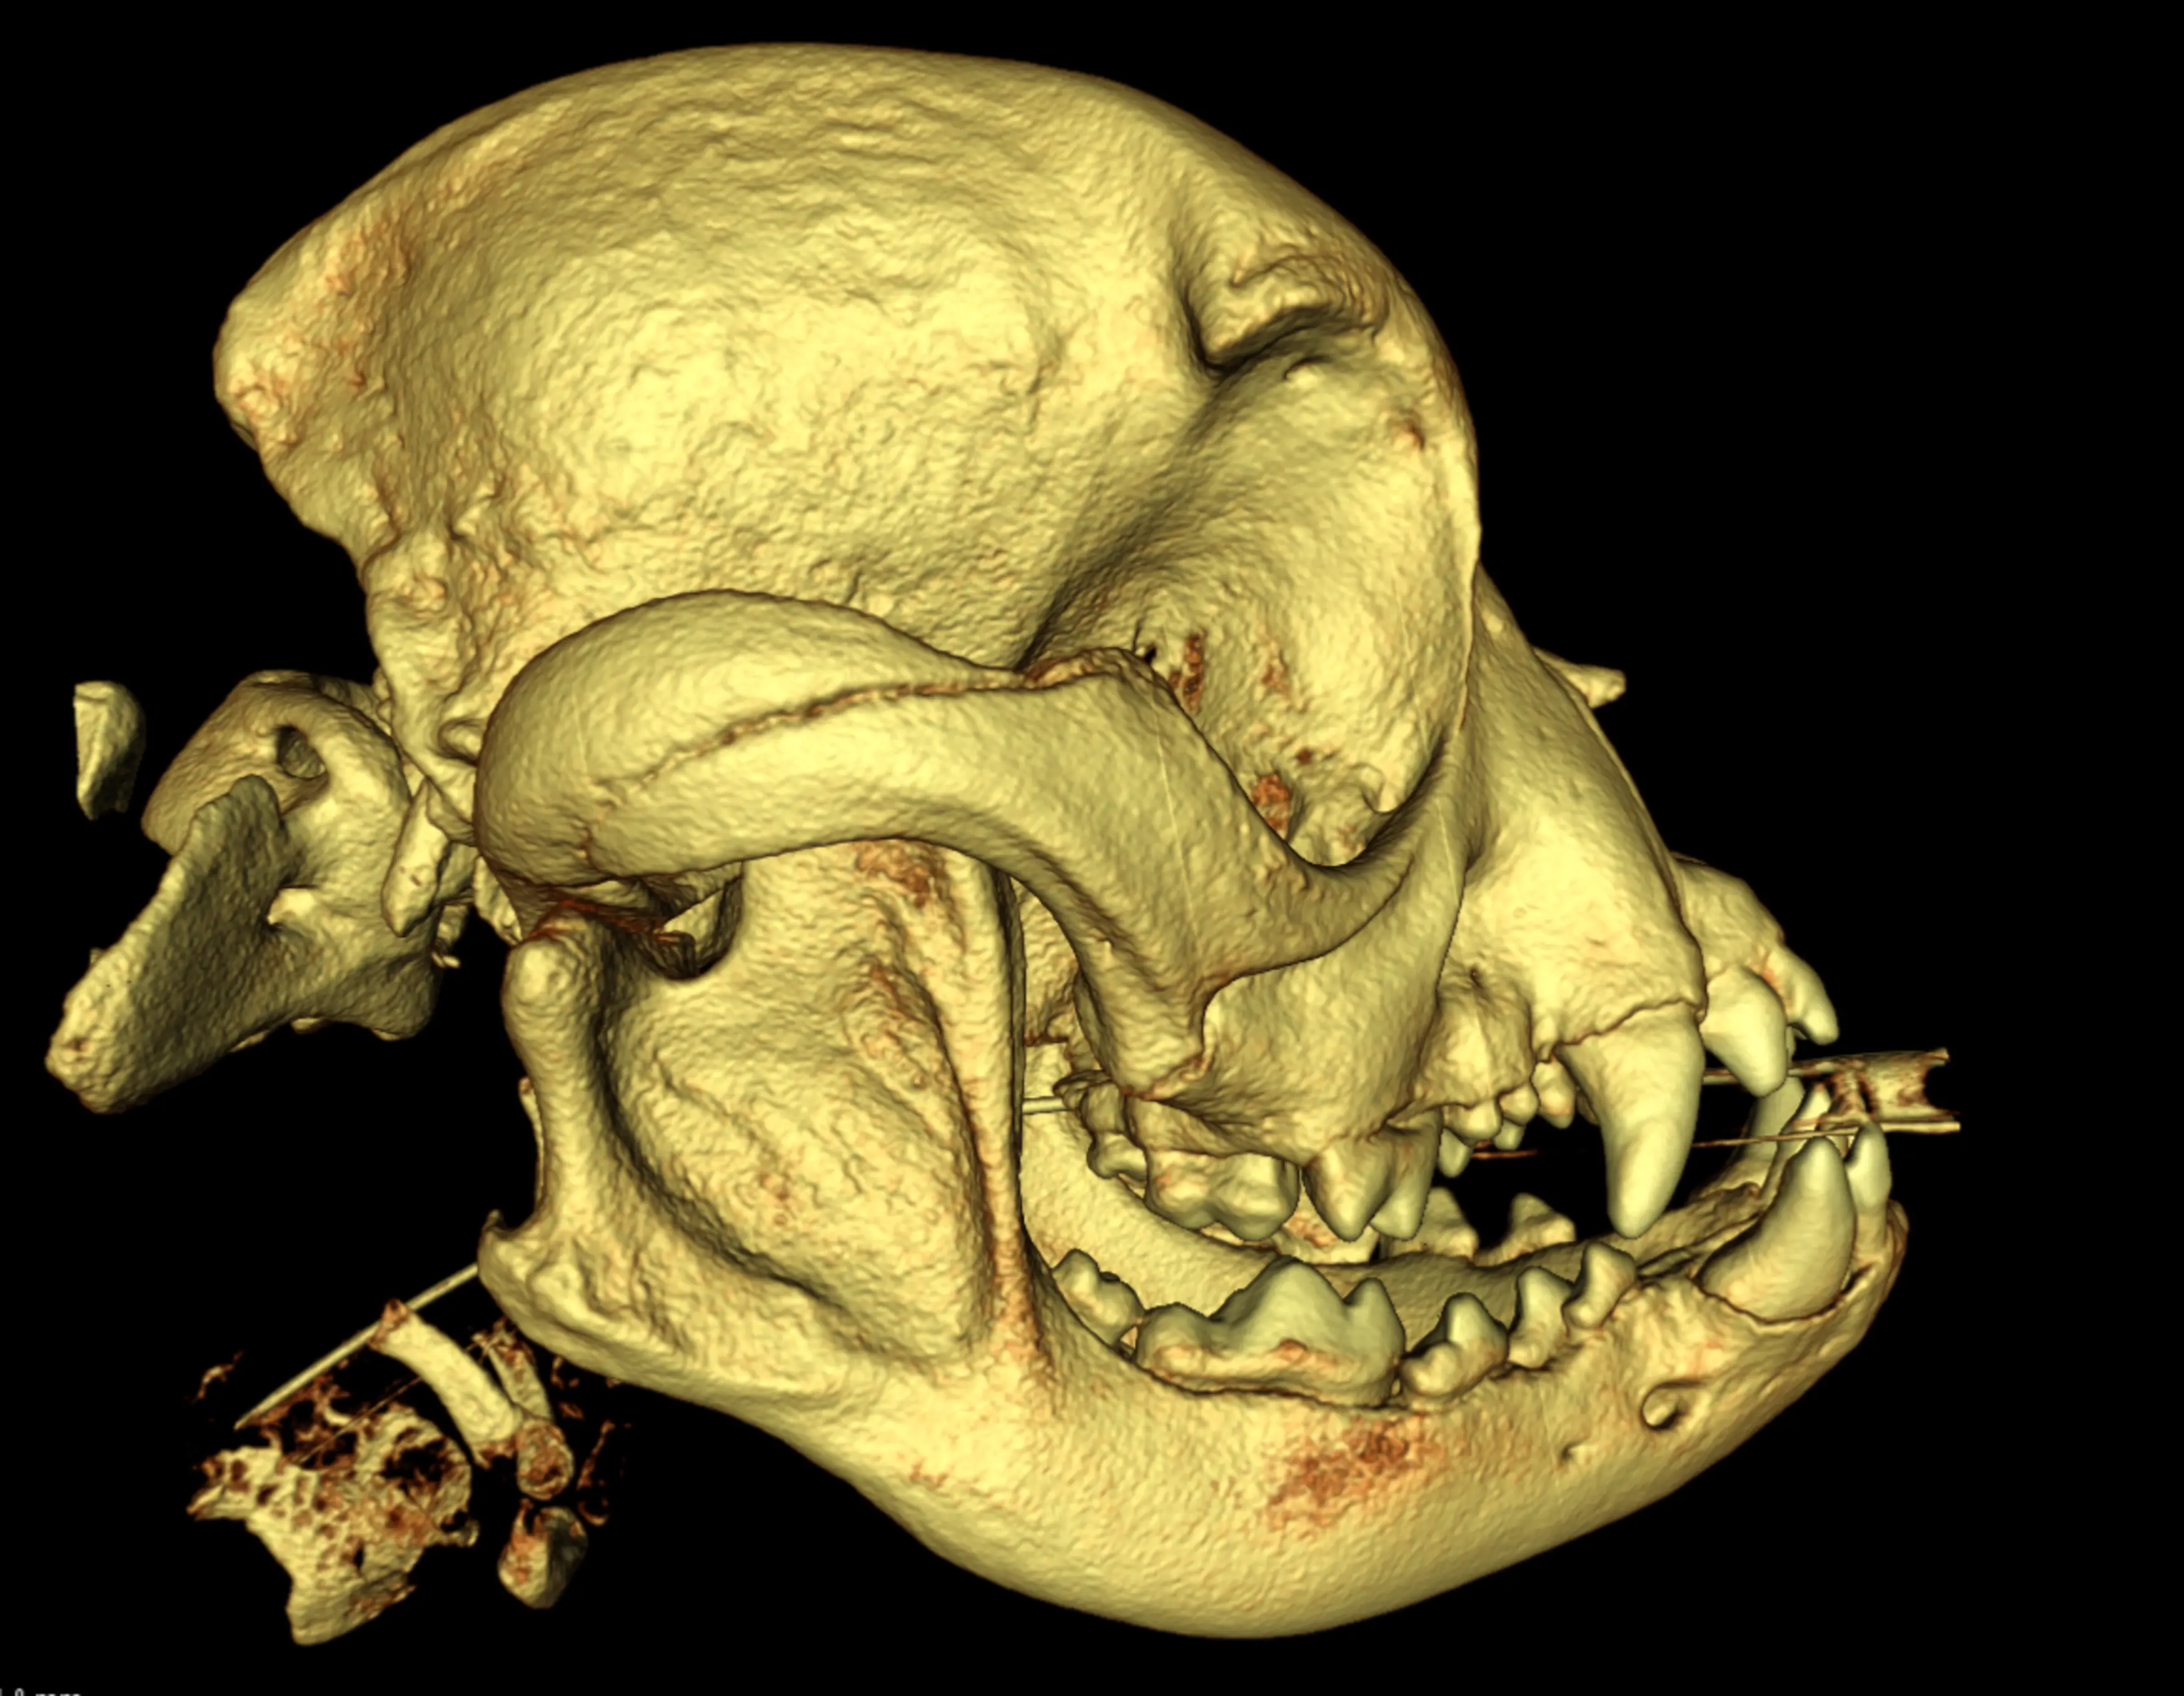

- Deformation des Schädels (z. B. französische Bulldogge)

Brachyzephale Hunde leiden häufig an Augenproblemen. In vielen Fällen ist entweder zu wenig Tränenflüssigkeit vorhanden oder die Zusammensetzung des Tränenfilms ist nicht gut. Die Folge sind dauerhaft gereizte Augen, Bindehautentzündungen und Hornhautdefekte, die eine lebenslange Therapie mit Augenmedikamenten nötig machen. Nicht selten sind auch hier kostenintensive Operationen notwendig. Weitere Operationskosten entstehen, wenn die Französische Bulldogge für die Rasse typische Erkrankungen des Bewegungsapparats mitbringt. Vertreter dieser Rasse neigen zu Keil-, Block- und Schmetterlingswirbeln. Eine Folge dieser Anomalien ist häufig ein Bandscheibenvorfall, dessen Diagnose mittels CT und dessen chirurgische Behebung Kosten in Höhe von knapp 4.000 Euro verursachen kann.